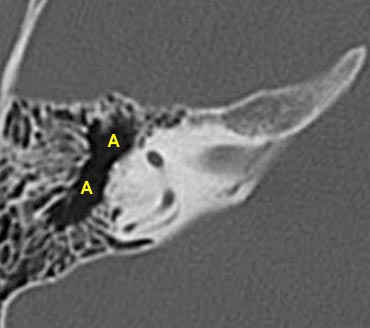

- A = Hang chũm (Antrum)

Ở mức này, ống thông hang (aditus ad antrum) được thấy rõ. Đây là đường thông nối giữa hòm nhĩ và hang chũm.

Hang chũm

Ở mức này, hang chũm được thấy bao quanh bởi các tế bào khí chũm nhỏ hơn, nằm ngay bên ngoài các ống bán khuyên trên.